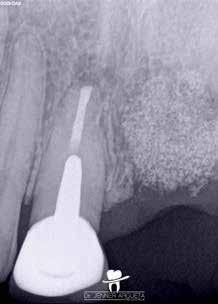

Az 56 éves férfi pácienst a bal alsó bölcsességfoga (38) endodonciai kezelésének céljából irányították dr. Witkowski rendelőjébe. A fog anatómiai helyzete és a páciens korlátozott mértékű szájnyitása megnehezítette a hagyományos módszerekkel történő endodonciai ellátás kivitelezését. A kezelés megtervezéséhez periapikális röntgenfelvétel készült és a fog belső anatómiai felépítését ezen felvétel segítségével vizsgáltuk (21. ábra). Az endodonciai kezelési tervet a vizsgálati eredmények alapján határoztuk meg.

A hozzáférési nyílás a referálást végző fogorvoskolléga által már előzetesen kialakításra került. A fogbélkamra inspekciója során visszamaradt pulpaszövetet észleltünk (22. ábra) A gyökércsatorna-bemenetek pontos lokalizációja előtt ezt még feltétlenül el kellett távolítani. Ez bármely endodonciai kezelés esetében érvényes, és a standard protokollunk része, mivel ellenkező esetben a pulpakamrában lévő törmeléket a gyökércsatornák mélyére juttathatjuk. Ehhez egy 2,780 nm-es hullámhosszon alkalmazott RFPT5–10 végződéssel ellátott (23. ábra) Er,Cr:YSGG lézer készüléket (Waterlase, BIOLASE) használtunk. A protokoll szerint ezen beavatkozás során először 1 percen keresztül folyamatos aktivációt végzünk, majd 1 percen keresztül nyugalomban hagyjuk a pulpakamrában lévő folyadékot (24. ábra). Csupán a fogbélkamrában lévő szövetek maradéktalan eltávolítását követően kezdhetjük meg a gyökércsatornák mechanikai feltágítását. A fogbélkamra megtisztítását követően (25–26. ábra) egy forgómozgást végző gépi gyökértágítót használtunk a gyökércsatorna megmunkálására. Ez ebben az esetben egy 12.5/.04 R-PILOT (VDW) gépi tű volt (27. ábra). A gyökércsatorna-rendszer belső anatómiai felépítésére és a szűk gyökércsatornákra való tekintettel hoztuk meg azt a döntést, hogy kizárólag ezt az egy tűt használjuk a mechanikai megmunkálás során. A feltágítás során a ki-be (in-out) technikát alkalmaztuk. Az egyes tágítási fázisok között nagy volumenű átöblítést és lézeres aktiválást végeztünk. A végső átöblítés során az aktiválást egy RFPT5–10 végződéssel ellátott Er,Cr:YSGG lézerrel végeztük (28–29. ábra).

A csatornák ezt követően készen álltak a gyökértömés elkészítésére (30–31. ábra. A gyökértömést a csatornába fecskendezett (cavit piston technique) VDW.1Seal biokerámiai sealer (VDW) segítségével készítettük el (32–34. ábra). A gyökértömés elkészítését követően kontrollröntgen készült (35. ábra). A beavatkozás során alkalmazott „lézer-asszisztált” endodonciai protokollnak köszönhetően képesek voltunk az egyébként mechanikai eszközökkel elérhetetlen laterális csatornákat is megfelelő módon megtisztítani és letömni. Az Er,Cr:YSGG lézerrel aktivált átöblítőszerek áramlási tulajdonságainak köszönhetően ez a rendkívül konzervatív mértékű feltágítás is elegendő volt a klinikailag sikeresnek imponáló gyökértömés elkészítéséhez.